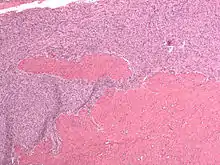

Micrograph of a low-grade endometrial stromal sarcoma. H&E stain.

Low-grade endometrial stromal sarcoma consists of cells resembling normal proliferative phase endometrium, but with infiltration or vascular invasion. These behave less[3] aggressively, sometimes metastasizing, with cancer stage the best predictor of survival. The cells express estrogen/progesterone-receptors.

• Monotonous ovoid cells to spindly cells with minimal cytoplasm.

• Prominent arterioles. Angiolymphatic invasion common.

• Up to 10-15 mitotic figures per 10 HPF in most active areas.

• Tongue-like infiltration between muscle bundles of myometrium.

• May exhibit myxoid, epithelioid and fibrous change.

• May have foam cells or hyalinization in the stroma.